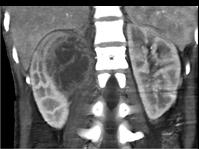

问题 女,32岁,右腰部疼痛伴高热,请根据所示图像,选择最可能诊断 ( )

选项 A、右肾囊肿合并感染 B、右侧急性肾盂肾炎 C、右肾结核 D、右肾脓肿 E、右肾囊性肾癌

答案 D